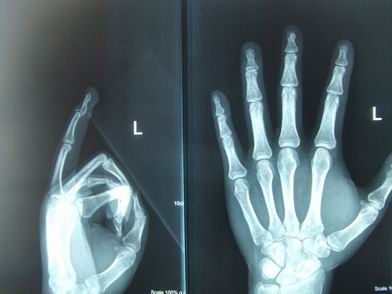

[讨论]先天性锤状指畸形